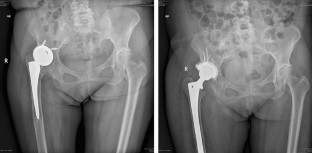

Preoperative acetabular cup templating has an important auxiliary effect on hip surgery. The traditional acetabular cup templating method requires the measuring person to have some experience in total hip replacement (THA) surgery since the measurement results vary from person to person with differences between different measuring persons. To obtain stable templating results, we designed a new acetabular cup templating method and tested the inter-person measuring differences and measurement accuracy of this method. Meanwhile, the clinical application of this method was preliminarily explored.

The pattern of this new method was manual labeling of imaging characteristic points and then programmed automatic measurements. The measurement process was performed entirely by orthopedic graduate students without any experience in hip replacement surgery. The inter-person measuring difference was evaluated by comparing the templating results of three measuring persons. The accuracy of the templating was evaluated by comparing the templating results with the actual size of the prosthesis in the surgery. The correlation between the position of the acetabular cup and the templating error was analyzed to explore the clinical significance of the templating results. This study was a retrospective study which included templating in a total of 406 cases for total hip replacement with cementless cup prosthesis. Digital measurements were performed using the Matlab software from MathWorks. The statistical comparison was performed using Kendall’s W test.

The results of the three measuring persons were completely identical in 61.8% (251/406) of cases, and the variation in 38.2% (155/406) of cases did not exceed one size of the acetabular cup. The Kendall’s W coefficient was 0.977, and p < 0.01. The measurement accuracy is not as good as the traditional method in exactly accurate measurement and ±1 cup size, but it is similar to the traditional method in the ±2 cup sizes. The correlation between the templating error and the position evaluation of the implanted acetabular cups reveals: (1) larger the templating error, larger the proportion of the acetabular cups with poor position; (2) the proportion of acetabular cup with poor position slowly increased when the templating error was from 0 to 1 size, and the proportion rapidly increased when the templating error was from 1 to 2 size.

All the patients with clear teardrop bottom and lateral superior edge of acetabulum were able to use our method to predict the size of the acetabular cup. The method has the following advantages: (1) it does not require the measuring person to have any previous experience of the THA surgery, which reduces the labor cost of the templating; (2) the differences between the measuring persons is small, the measurement result can be repeated; (3) it can predict the probability of acetabular cup with poor positioning according to the templating error, and thereby reminding the surgeon to recheck and correct the position of the acetabular cup in time during the surgery.